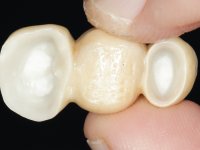

Teeth 17 and 16 were prepared for the fabrication of a 2-element Zr bridge. The impression was performed with a double mixing technique and a monolithic bridge in Zr was made in the laboratory. 4 years later, an abscess appeared in the apical area of tooth 26. It was decided to remove the bridge, remove the intra-radicular posts and retract the endodontic treatments of teeth 17 and 16. The removal of the bridge was carried out by making two cervical cavities. in the palatal area of the bridge and with a microluxator, disinsertion movements were performed. The intra-radicular posts were removed using fine drills and an ultrasound tip. The bridge was provisionally cemented and the patient was referred to a fellow endodontist for endodontic retreatment. After the retreatment, the intraradicular posts were placed again and the bridge was definitively cemented. One year later, a new abscess appears, possibly related to a root fracture. The bridge was sectioned between tooth 27 and 26 and tooth 26 was extracted and the crown of 27 was provisionally cemented. 3 months later, teeth 27 and 25 were prepared and a temporary bridge was made in dual polymerization resin. Then, an impression was made using the double mixing technique and a 3-element bridge in Zr was made in the laboratory. It was permanently cemented in the mouth with resin-reinforced glass ionomer cement.